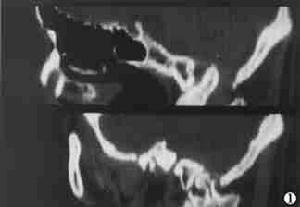

放射學檢查以枕骨大孔區為中心的顱-頸正側位片、體層攝片、前後位開口攝片(檢查寰、樞椎)、顱底攝片(檢查斜坡、齒狀突)等顱腦平片。通常顱-頸側位片即可確診是診斷顱底凹陷症最簡單的方法。必要時可行CT掃描、矢狀面重建則對枕骨大孔區的畸形觀察更為清楚另外可根據病情選擇脊髓造影氣腦造影腦室造影和腦血管造影等。

2、CT掃描主要是顯示腦組織及腦室的改變有時可行腦室造影CT掃描在腦室內注入非離子水溶性造影劑後行CT掃描可觀察到腦室大小中腦水管是否通暢及第四腦室及腦幹的改變,並可勾畫出小腦扁桃體下緣的位置